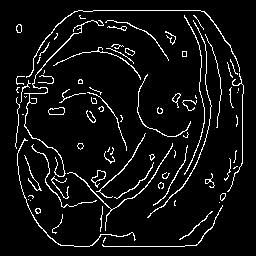

The performance metrics for Edgeconnect and AOTGAN on the validation data after fine-tuning the models, are shown in Table II. In addition to qualitative evaluation, Figure 3 provides example data from the different steps of the PolypConnect pipeline using the EdgeConnect model and the AOTGAN model. Due to obvious visual differences in the generated polyps between the models, we selected the EdgeConnect model as the main polyp inpainting model of the PolypConnect pipeline for further evaluation and qualitative assessment by domain experts.

(a) Refer to caption Refer to caption Refer to caption Refer to caption Refer to caption Refer to caption

(b) Refer to caption Refer to caption Refer to caption Refer to caption Refer to caption Refer to caption

(c) Refer to caption Refer to caption Refer to caption Refer to caption Refer to caption Refer to caption

(d) Refer to caption Refer to caption Refer to caption Refer to caption Refer to caption Refer to caption

(e) Refer to caption Refer to caption Refer to caption Refer to caption Refer to caption Refer to caption

(f) Refer to caption Refer to caption Refer to caption Refer to caption Refer to caption Refer to caption

(g) Refer to caption Refer to caption Refer to caption Refer to caption Refer to caption Refer to caption

(h) Refer to caption Refer to caption Refer to caption Refer to caption Refer to caption Refer to caption

Figure 3: Sample data used and generated in the different steps of PolypConnect pipeline. (a) - real polyp images, (b) - manually annotated polyp masks, (c) - randomly selected colon images used as input to the final step of PolypConnect, (d) - extracted edge images of row c. (e) - extracted edge images of polyp regions of row a using the masks of row b. (f) - combined edge images of row d and f. (g) - generated polyp on the images of row c using EdgeConnect. (h) - generated samples from AOTGAN.